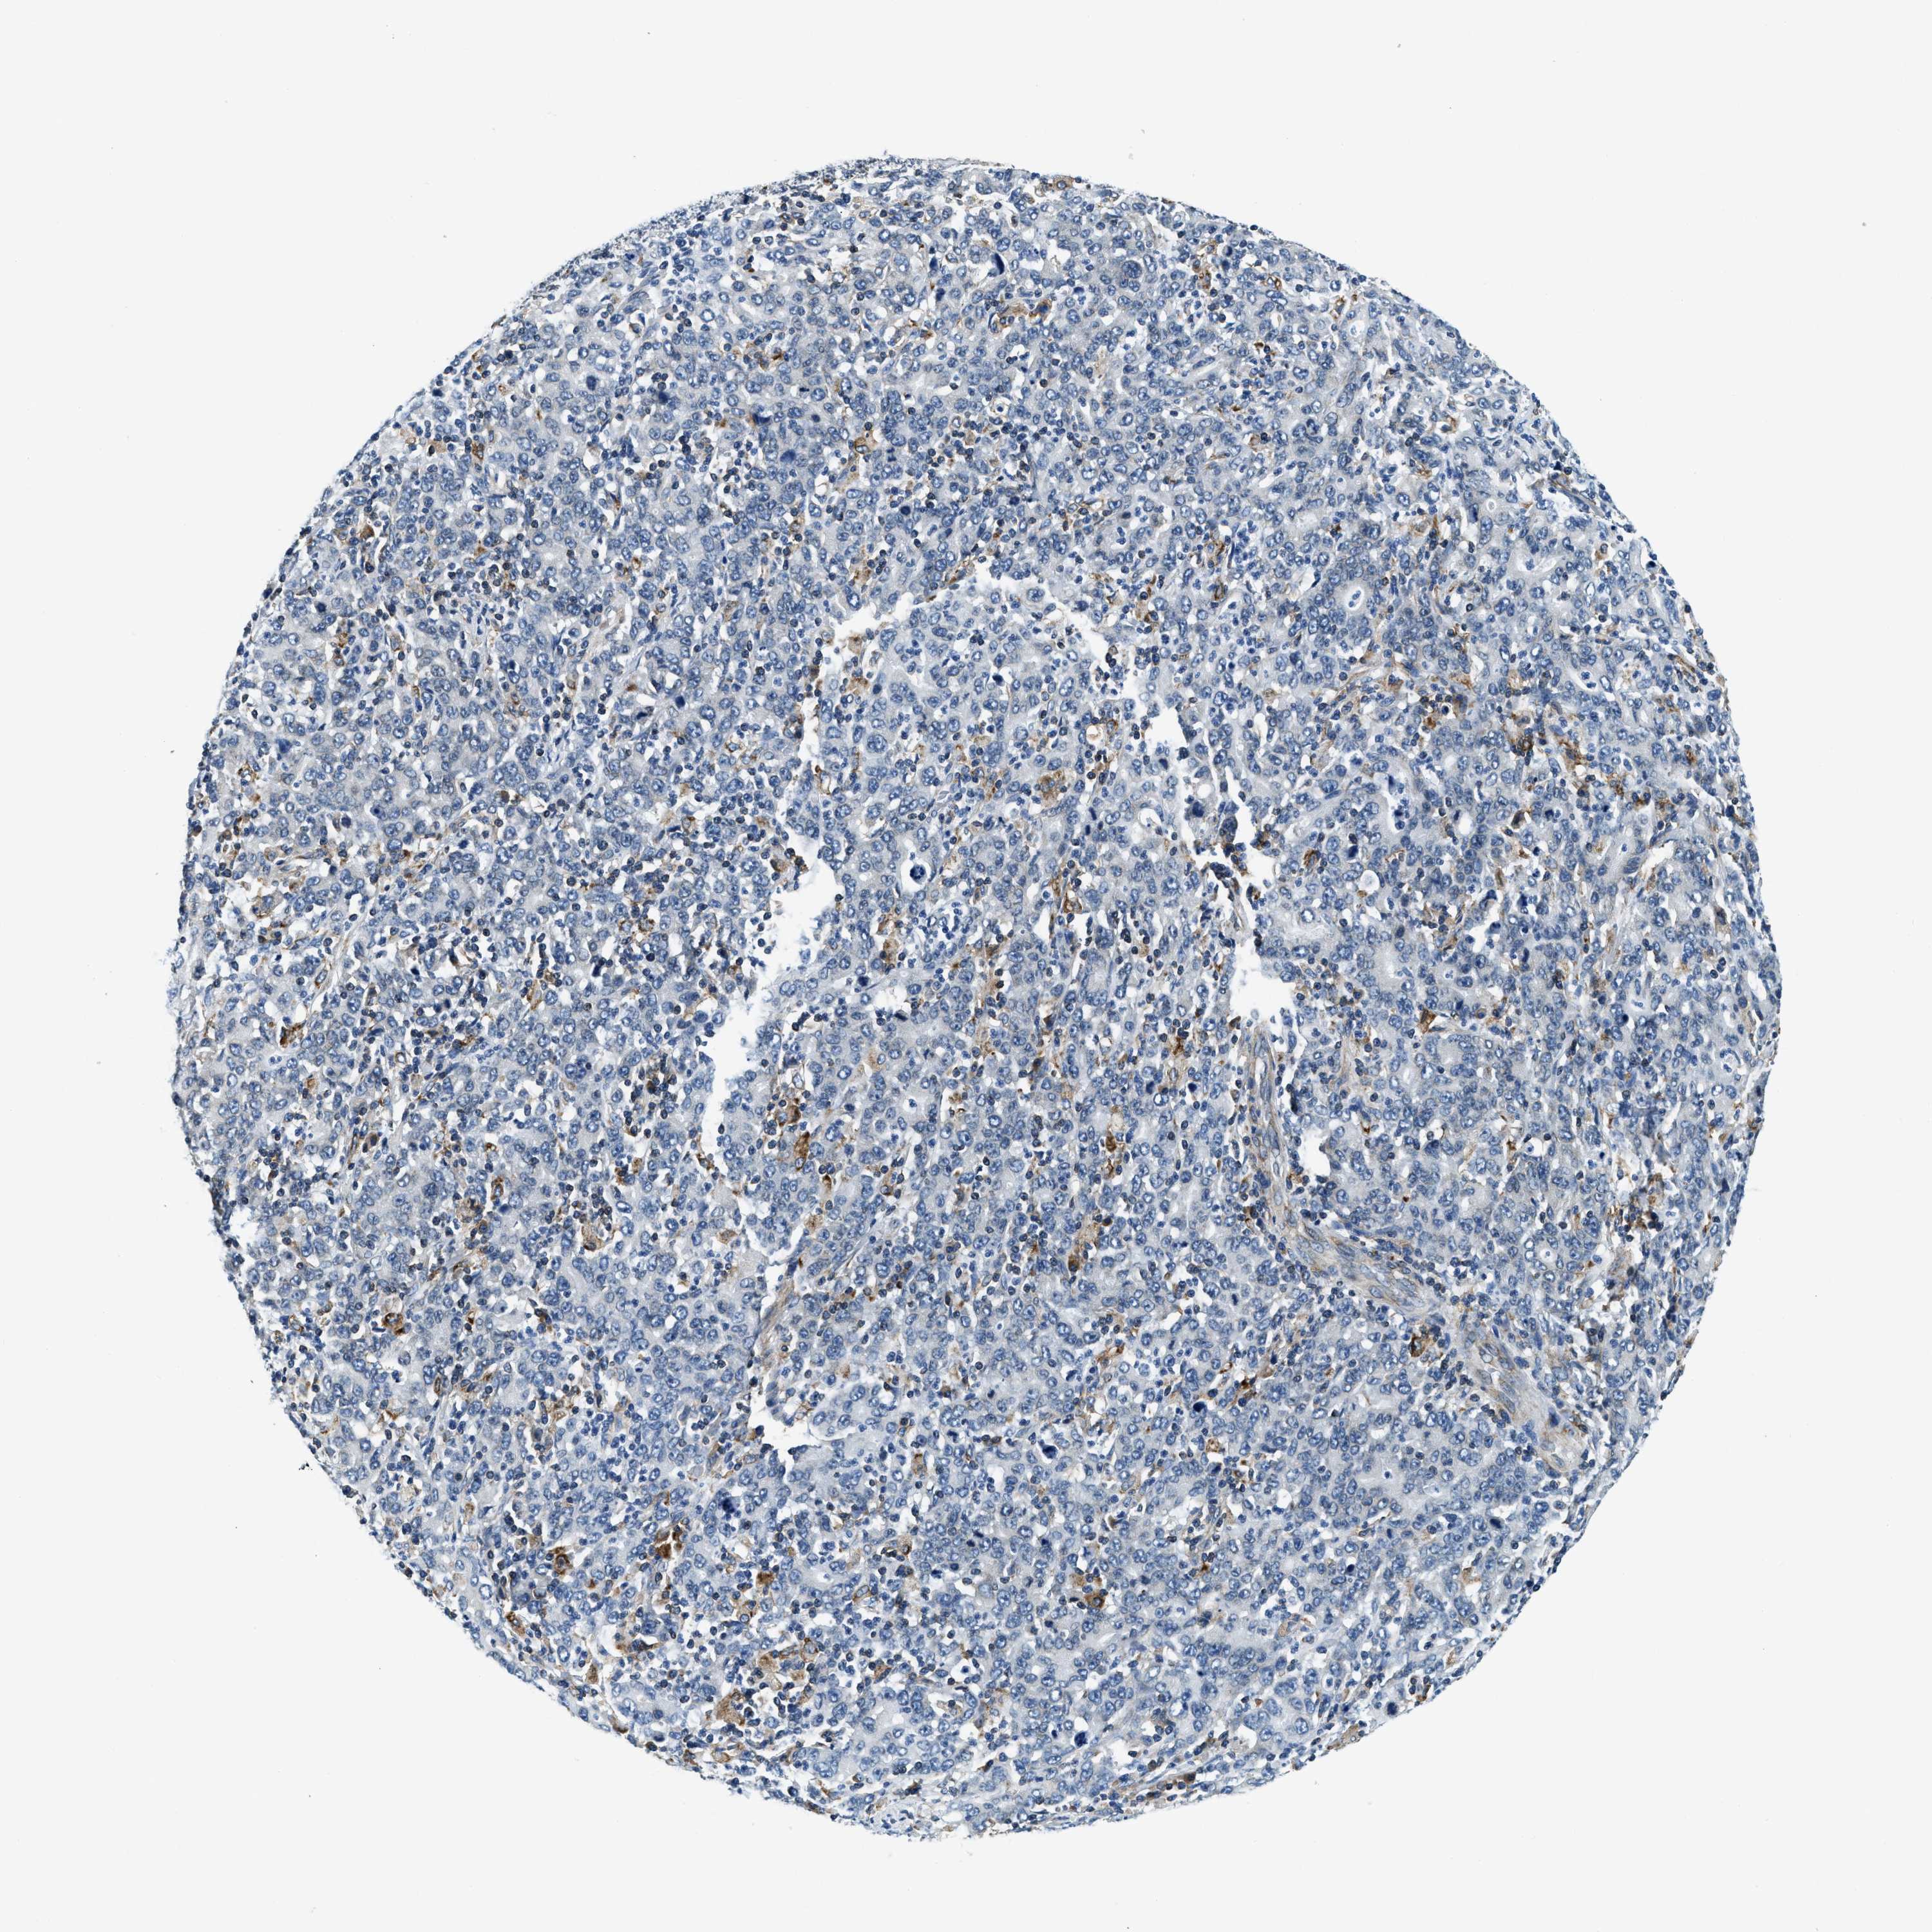

STOMACH CANCER - Protein expressioni

A mouse-over function shows sample information and annotation data. Click on an image to view it in a full screen mode. Samples can be filtered based on level of antibody staining by selecting one or several of the following categories: high, medium, low and not detected. The assay and annotation is described here.

Antibody stainingi

Antibody staining in the annotated cell types in the current human tissue is reported as not detected, low, medium, or high, based on conventional immunohistochemistry profiling in selected tissues. This score is based on the combination of the staining intensity and fraction of stained cells.

Each image is clickable and will lead to virtual microscopy that enables deeper exploration of all samples and also displays staining intensity scores, fraction scores and subcellular localization as well as patient and tissue information for each sample.

Antibody HPA019698

Staining

High

Medium

Low

Not detected

Intensity

Strong

Moderate

Weak

Negative

Quantity

>75%

75%-25%

<25%

None

Location

Nuclear

Cytoplasmic/membranous

Cytoplasmic/membranous,nuclear

Adenocarcinoma, NOS